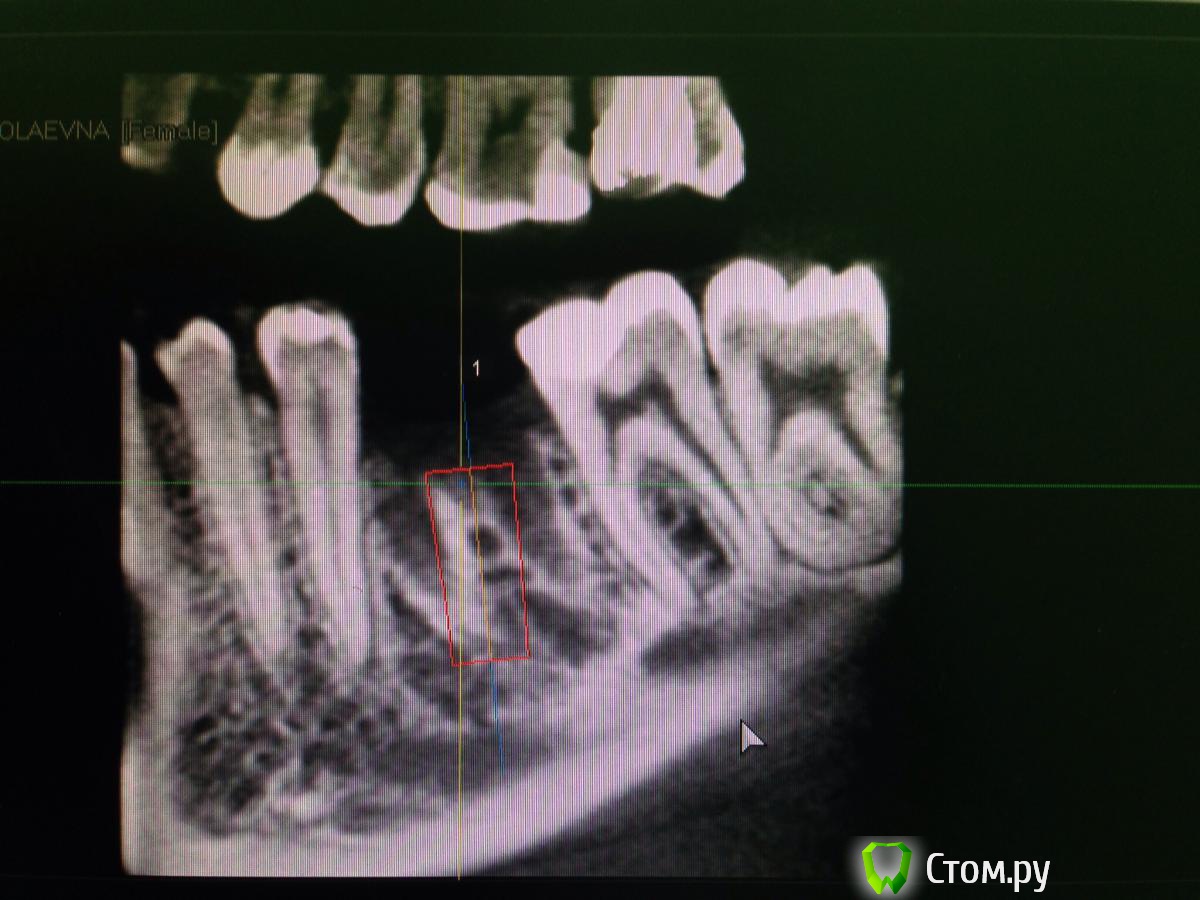

diesel87 Опубликовано 10 февраля, 2014 Поделиться Опубликовано 10 февраля, 2014 Планируется установка винта в области удаленного 3 месяца назад 36 зуба, размером 4,8*12; вот срезы кт, винт планирую в такой позиции, волнует костная пластика, нужна ли она и где именно и не слишком ли глубоко будет стоять винт по отношению к соседним зубам? Ссылка на комментарий

syrovovec Опубликовано 10 февраля, 2014 Поделиться Опубликовано 10 февраля, 2014 12 у вас в плотную к каналу,при такой постановке у знакомый доктор получил онемение.на следующий день выкрутил на пол витка.продолжения не знаю 1 Ссылка на комментарий

Sahan Опубликовано 10 февраля, 2014 Поделиться Опубликовано 10 февраля, 2014 Учитывая что Вам нужно на 1 мм утопить имплантат, а на крайнем фото до канала осталось около 2 мм, 12 мм будет впритык к каналу. Что , как писал коллега выше, может боком вылезти. Ссылка на комментарий

kriokov Опубликовано 10 февраля, 2014 Поделиться Опубликовано 10 февраля, 2014 крутите 4.2 х 10, если кореец, субкрестально на 1 мм, и по переферии кости больше останется, и до канала нормально.В лунке минерализации нет, прошло только 3 мес. Если почувствуете, что пилотник очень легко на всю глубину прошел, дальше можно остеотомами МИсовскими, Ссылка на комментарий